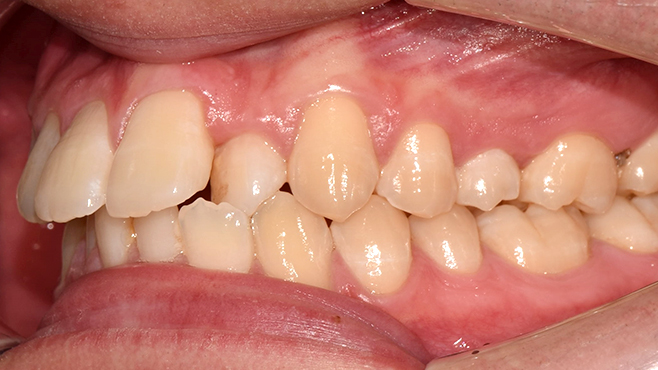

5060 시니어 임플란트

건강하고 오래가는 시니어 임플란트,

치료 사례부터 남다릅니다.

before

after

※ 위 임상사진은 동일조건으로 촬영되었으며, 사진에 대한 별도의 조작이 처리되지 않았습니다.

※ 위 임상사진 및 포트레이트는 환자와의 포괄적인 초상권 계약 이후 사용하고 있습니다.

※ 수술 및 치료과정에서 부작용이 발생할 수 있으므로 충분한 상담과 신중한 판단이 요구됩니다.

실제 치료 사례

수많은 환자들이 고민 끝에 선택한 치료,

그리고 그 후의 놀라운 변화

- ※ 위 임상사진은 365서울원탑치과에서 진료를 시작하고 마친 동일한 환자의 사진입니다.

- ※ 위 임상사진은 동일한 장소에서 동일한 조건으로 촬영되었으며, 사진에 대한 별도의 조작이 처리되지 않았습니다.

- ※ 수술 및 치료 과정에서 부작용이 발생할 수 있으므로 의료진과의 충분한 상담과 신중한 판단이 요구됩니다.